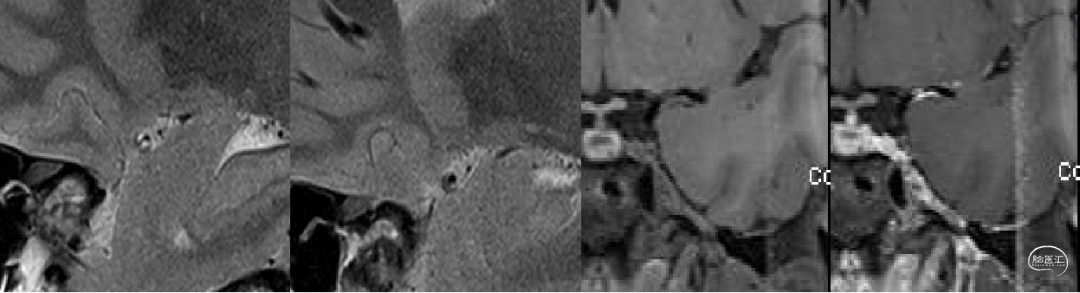

高分辨 MRI:

虽该患者较为年轻,但药物控制不佳的症状性颅内动脉狭窄患者还是较为常见,但是高分辨磁共振提示左侧大脑中动脉M1段病变为动脉粥样硬化性偏心性斑块,增强有斑块有明显强化,提示为易损斑块,狭窄程度严重,结合患者有长期吸烟史且经过药物治疗后仍不能控制,故该患者有介入治疗的指征。从术中影像中也能看出术者手术功底扎实。

从6个月复查结果看到大脑中动脉穿支似乎较术前和术后即刻DSA有所减少,希望术者解释其原因并提供更多的动态影像信息,提供随访磁共振影像和临床随访结果。